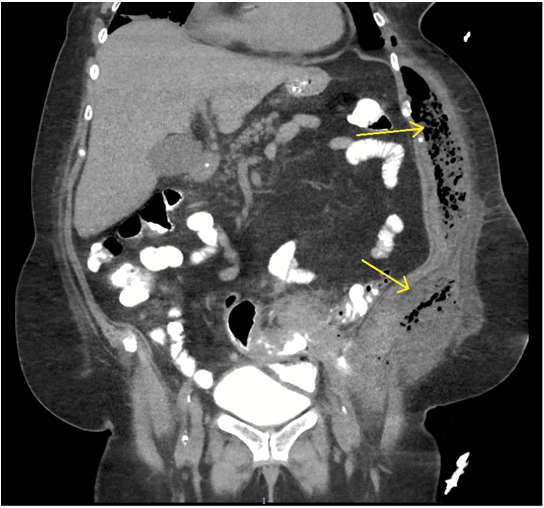

Figure 1. Inflammatory changes about the sigmoid colon with a fistulous connection to the left lateral abdominal wall with a large collection of air, fluid and likely fecal material (yellow arrows).

A 67-year-old, morbidly obese female presented to the emergency department with a two-week history of fatigue and left-sided flank pain. Her medical history included breast cancer treated three years prior with chemoradiotherapy and radical mastectomy and chronic iron deficiency anemia. Her risk of developing colorectal cancer was considered that equal to the general population and she did not undergo routine screening. Patient was a non-toxic appearing, obese female with tender fluctuance along her left flank. Laboratory analysis showed microcytic anemia (hemoglobin-9.7 gm/mL, MCV-75), leukocytosis (total leukocyte count-14,800 cells/mm3), and acute kidney injury (creatinine 3.2 mg/dL, serum urea-88 mg/dL). Computed tomography without contrast showed a large subcutaneous air/fluid collection concerning for abscess along the left lateral abdominal wall with a fistulous communication to the sigmoid colon (Figure 1 and Figure 2). There were also inflammatory changes within the sigmoid colon with additional fistulas to the ileum and urinary bladder. The patient was started on intravenous fluids, antibiotics, and analgesics. Flexible sigmoidoscopy revealed a circumferential, obstructing, fungating, and friable sigmoid mass concerning for adenocarcinoma (Figure 3) which was confirmed by biopsy. Incision, drainage and washout of the flank abscess was performed for source control which yielded copious feculent material. Metastatic disease was absent on staging CT imaging thus surgical management with curative intent was pursued.